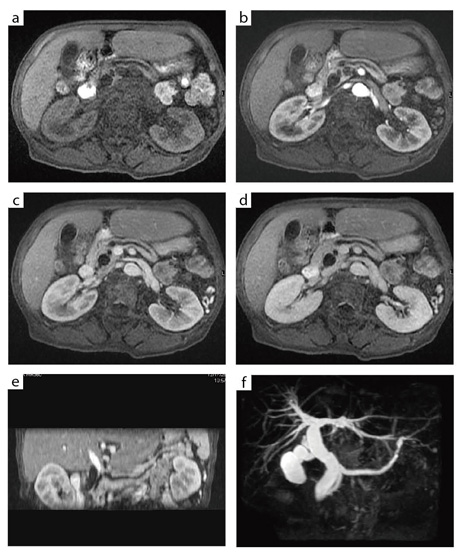

図6 LAVA によるダイナミック造影3D画像とMRCP

総胆管,主膵管の拡張を認める膵のIPMNが疑われ,MRIを依頼された症例(最終診断はついていない)。

a〜d:LAVAによるダイナミック造影脂肪抑制T1強調像(a:造影前,b:25秒後,c:55秒後,d:145秒後)。撮像時間は19秒で,呼吸停止下で3D画像を得ることができる。

e:55秒後の画像(c)から作成した,膵体尾部に沿ったcurved MPR画像。

f:3D-MRCPのMIP画像。総胆管,主膵管が全体に拡張している。